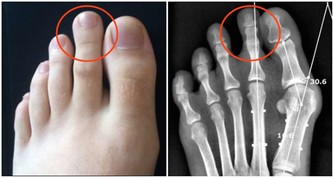

國外科學家研究發現,鎂可激活325個酶系統,把鎂稱為“生命活動的激活劑”是當之無愧的,而且,鎂對人的心臟血管具有重要的保護作用,人體如果缺鎂,就會導致心跳過速、心律不齊以及心肌壞死和鈣化等種種健康問題。